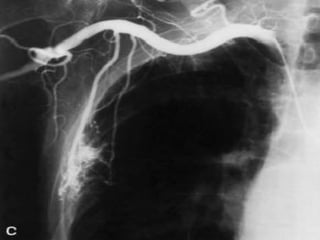

classical bronchial

artery patterns

40 %

2 left & 1 right

20 %

1 left & 1 right

2 left & 2 right

10 %

1 left & 2 right

( JC. van den Berg, 2006)

classical bronchial artery patterns 40% 2 left & 1 right 20 % 1 left & 1 right 20 % 2 left & 2 right 10 % 1 left & 2 right ( JC. van den Berg, 2006)